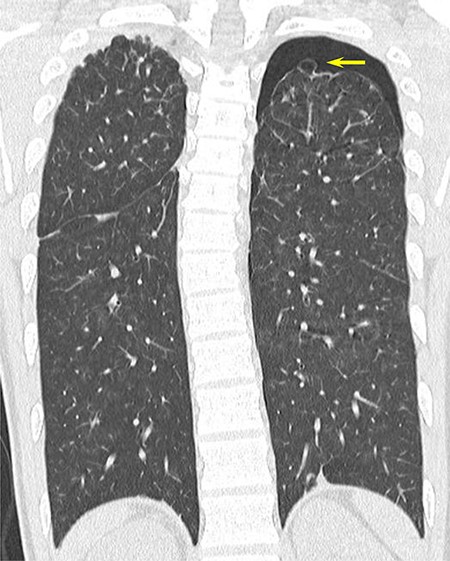

CT scan showing apical bullae on both sides of the upper lobe of the lung and left-sided pneumothorax.

recurrent intermittent epistaxis every few months and was monitored for PAVMs using computed tomography (CT) examinations every 6 months. He had a family history of HHT in his father and grandfather. After systemic examinations, he was diagnosed with HHT because he met the diagnostic criteria, including the presence of PAVM, recurrent epistaxis, and a family history of HHT, although genetic testing was not performed. A chest CT scan showed a left pneumothorax and apical bullae on both sides of the upper lobe (Fig. 1). In addition, a total of six PAVMs (four in the right lung, two in the left lung) were shown on the chest CT (Fig. 2). All PAVMs were located peripherally with the largest one being 3 mm in diameter. No AVM was detected in the brain or abdomen on CT. He was treated conservatively and then pneumothorax was improved. Six months later, the patient complained of cough and was diagnosed with pneumothorax by chest X-ray. To prevent the recurrence of the pneumothorax, the patient was offered video-assisted thoracic surgery. Intraoperatively, apical bullae and multiple telangiectasias were identified under the visceral pleura (Fig. 3). We performed wedge resection of the left upper lobe including the apical bullae. The postoperative histopathological findings of the resected specimen revealed pulmonary bullae (Fig. 4). The postoperative course was uneventful, and the patient was discharged on postoperative Day 2. He underwent catheter embolization for PAVMs in another hospital. His SpO2, which was measured before catheter embolization, was 97% on room air. There was no remarkable change in SpO2 after the intervention. No recurrence of the pneumothorax was observed during a 3-year follow-up.